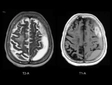

Epidural Beyin Kanaması Belirtileri ve Tedavisi